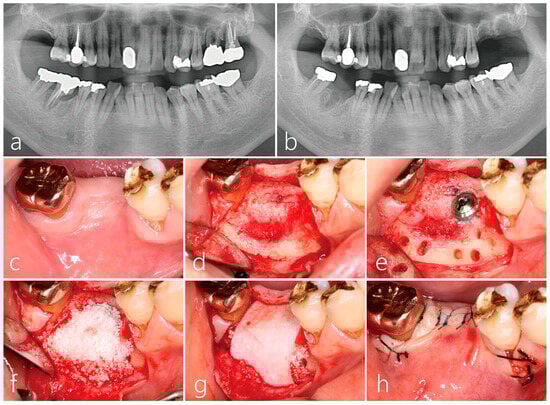

2.4. Surgical Reentry